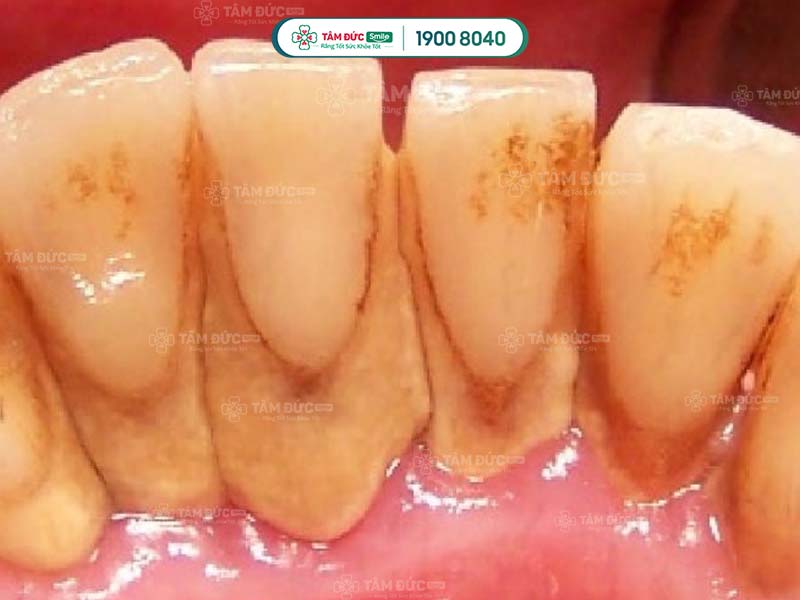

- Phát hiện có nhiều cao răng và mảng bám ở thân răng hoặc dưới nướu.

Cao răng tích tụ lâu ngày sẽ gây ra các bệnh lý như: Sâu răng, viêm nướu, tụt nướu, mòn men răng, viêm nha chu,... Do đó, cạo cao răng thường xuyên giúp Quý khách ngăn chặn vi khuẩn phát triển, giảm nguy cơ mắc phải các bệnh lý răng miệng.

Cao răng có màu sẫm, tích tụ trên thân răng làm ảnh hưởng đến thẩm mỹ nụ cười. Cạo cao răng giúp Quý khách loại bỏ các mảng bám tối màu, trả lại hàm răng trắng sáng và đẹp mắt hơn.

Vi khuẩn tích tụ trong cao răng thời gian dài sẽ tấn công vào sâu bên trong, làm hư hại răng và nướu nặng nề. Lâu dần, xương hàm của Quý khách có thể bị tiêu biến, tăng nguy cơ lung lay răng vĩnh viễn. Như vậy, cao răng nghiêm trọng có thể làm cho Quý khách đối mặt với vấn đề mất nhiều răng cùng lúc.